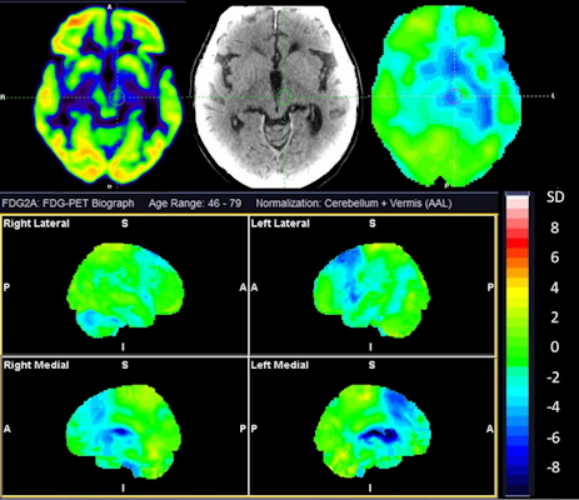

上圖為一名73歲男性的F-18 FDG-PET成像,伴有皮質(zhì)基底變性(CBD)和進(jìn)行性核上麻痹(PSP)的重疊特征。最上面一行顯示了F-18 FDG、CT和統(tǒng)計(jì)圖的基底神經(jīng)節(jié)和中腦水平的軸切面。最下面一行顯示了與健康受試者的標(biāo)準(zhǔn)差的統(tǒng)計(jì)表面投影。注意基底神經(jīng)節(jié)指向CBD的不對(duì)稱性和受累,中腦和內(nèi)側(cè)額葉皮質(zhì)指向PSP的受累。圖片和說(shuō)明由EJNMMI Research通過(guò)CC BY 4.0提供。